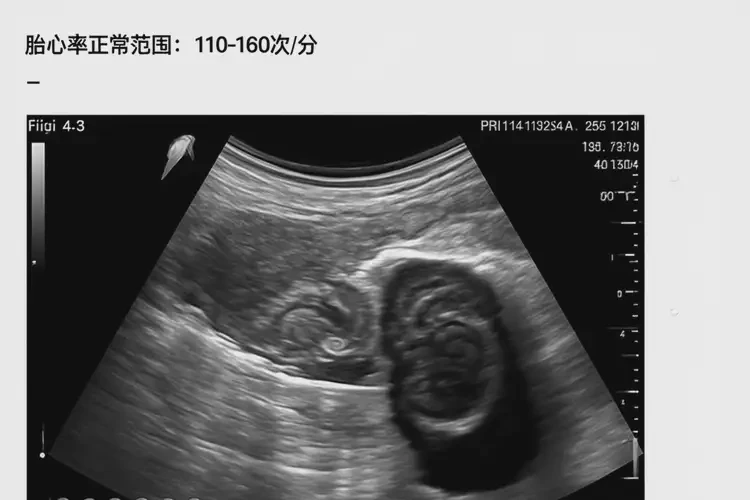

孕13周時(shí),正常胎心率范圍為110-160次/分鐘。胎心率85次/分鐘明顯低于正常值,可能提示胎兒存在缺氧或其他健康問題。僅憑一次胎心率測量結(jié)果無法確定胎兒是否能要,需要結(jié)合其他檢查和醫(yī)生的專業(yè)判斷。

• 孕早期(12周前):胎心率較快,通常在110-160次/分鐘之間。

• 孕中期(12-28周):胎心率逐漸穩(wěn)定,仍在110-160次/分鐘之間。